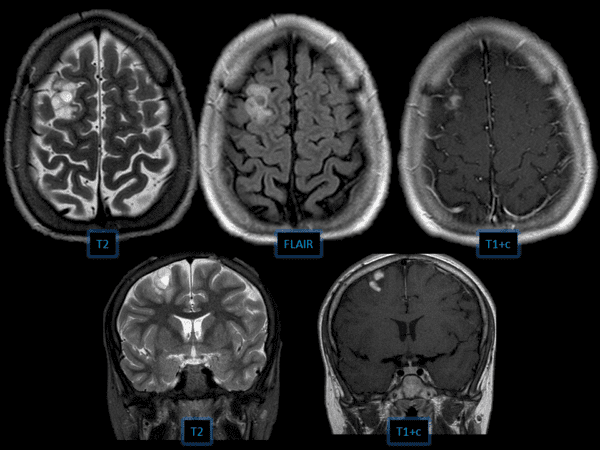

DNET

» Thông tin: Nam giới – 12 tuổi.

» Lâm sàng: Đau đầu.

Danh mục: Thần Kinh